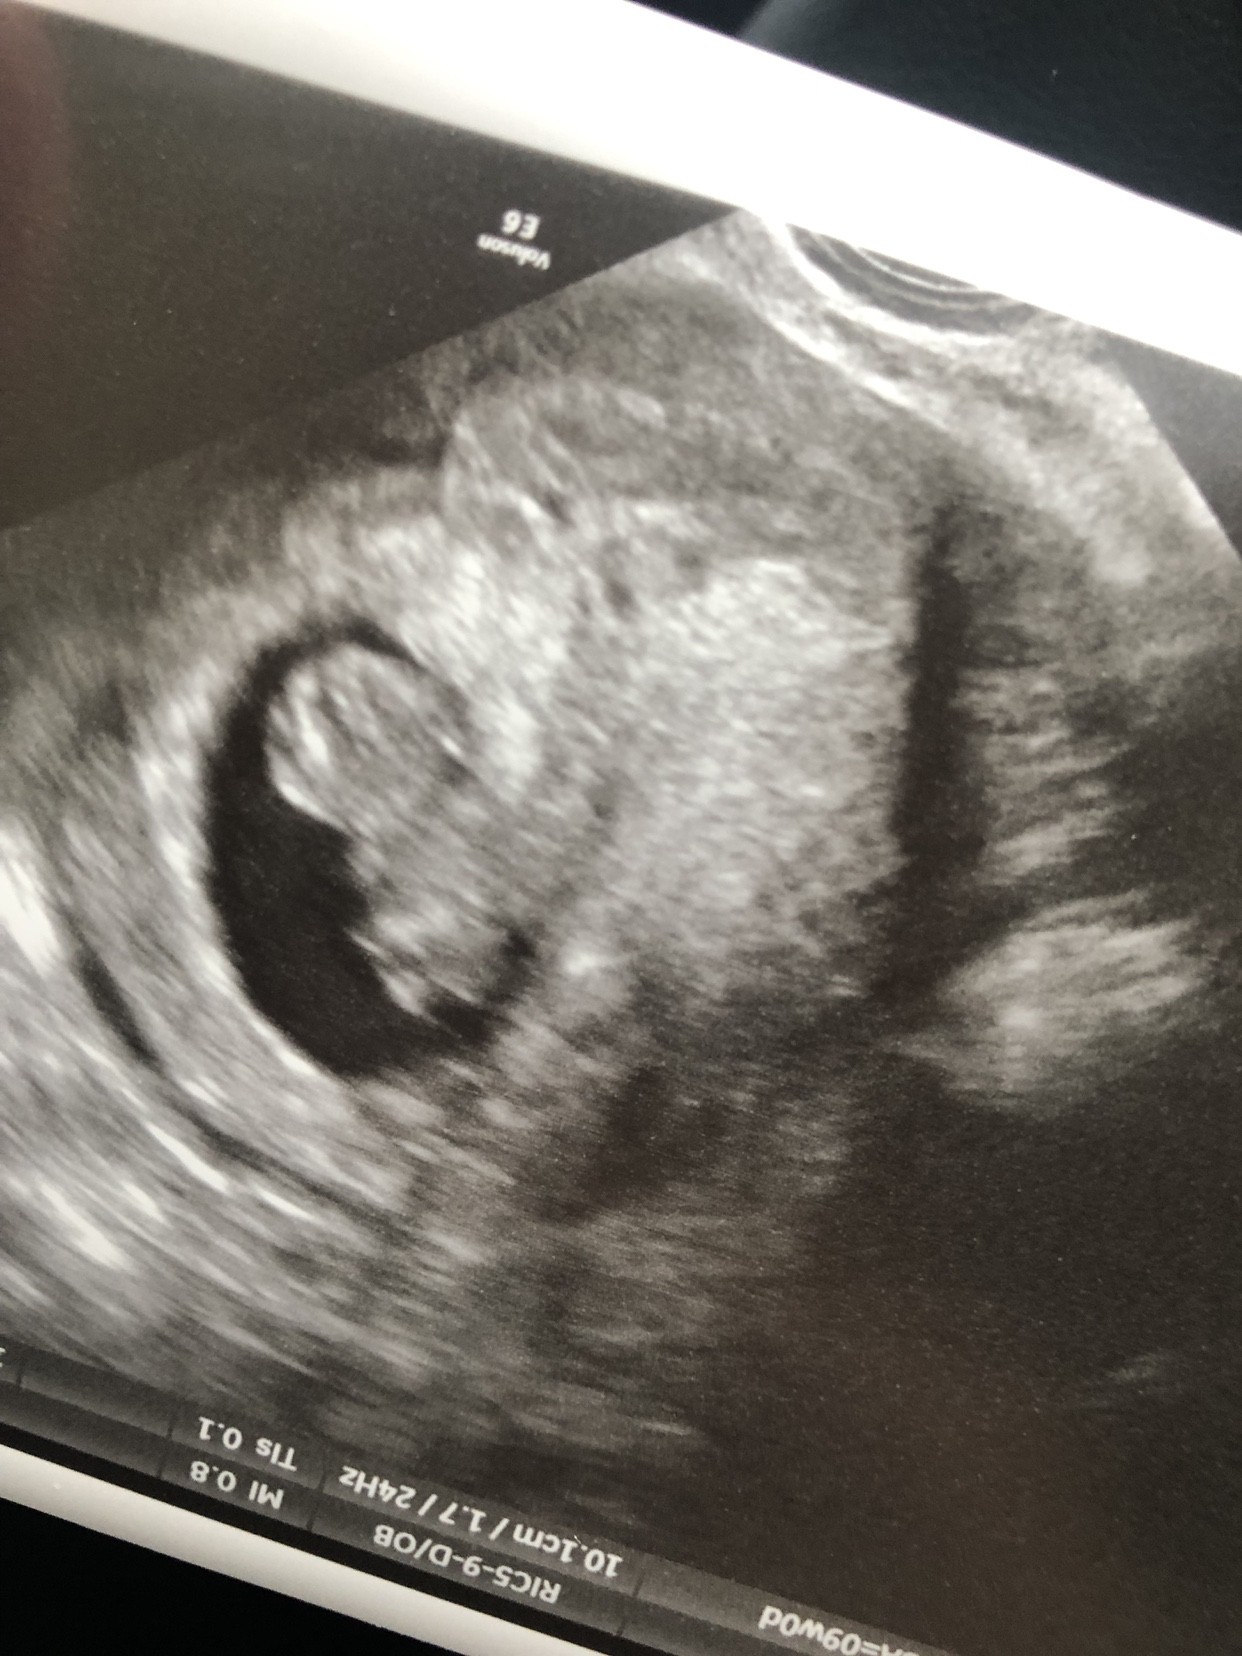

Witam się ja i moj dzidzius po wizycie.

Ma 2.5 cm i pięknie bijące serduszko.

Wyglada już jak mini człowiek.

Ruszał rączkami i kopał [emoji85]

Super szybko urósł i przeszłam na 9tydzien i 1 dzień :-)